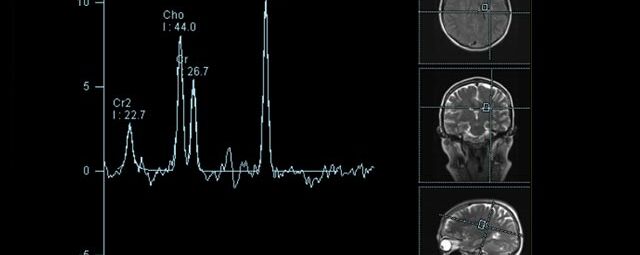

• Tumore, ggf. mit Spektroskopie

Spezialtechniken der Magnetresonanz

• MR-Spektroskopie

Diese Verfahren werden bei verschiedenen Fragestellungen in verschiedenen Körperregionen in die Messprotokolle sinnvoll eingefügt. Teilweise können dadurch Differenzierungenverschiedener krankhafter Prozesse verbessert werden.